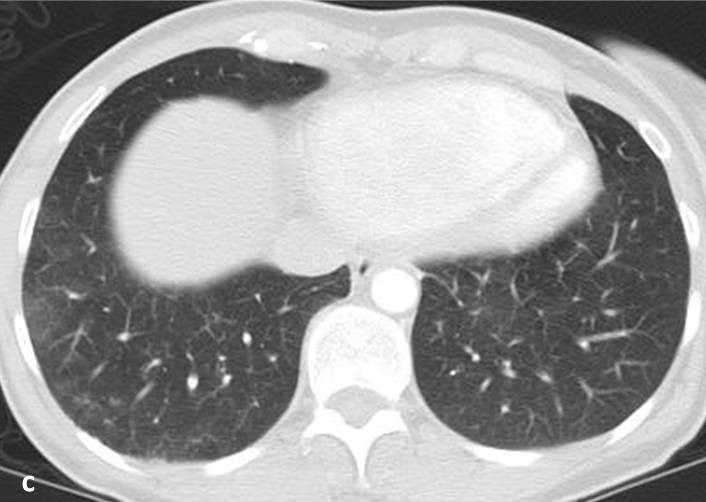

Histiozytosis X; z. T. konfluierende Zysten mit dünnen Wänden im Lungen-Oberfeld (a) und -Mittelfeld (b) unter Aussparung der Lungenbasis (c; Thorax-CT) |